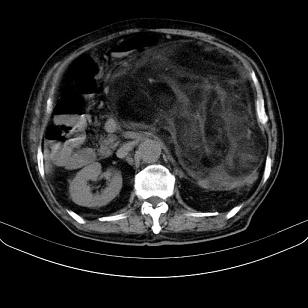

腹膜后高分化脂肪肉瘤

腹膜后脂肪肉瘤

左侧腹膜后脂肪肉瘤。